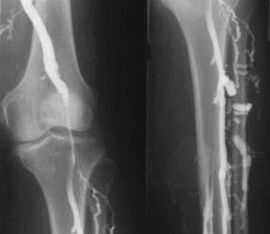

The most common instrumental diagnostic method is the use of ultrasound examination of the venous vessels of the legs.This technique allows you to visualize the vascular system and identify the degree of progression of the pathological process.

- Phlebography.

- Photoplethysmography.

The use of venous occlusion plethysmography makes it possible to determine the volume of blood in the veins of the lower extremities.